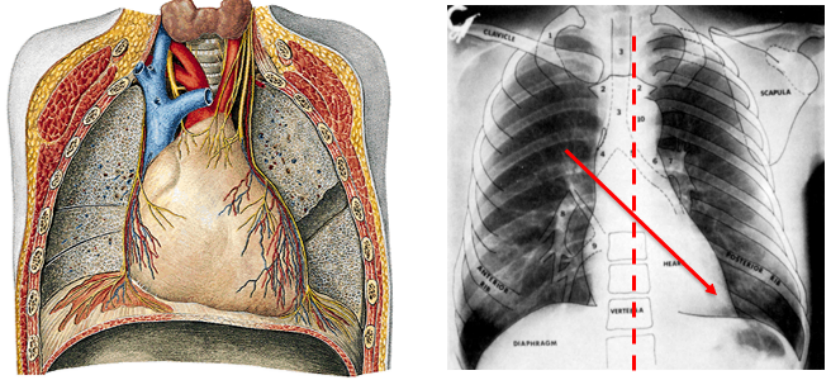

1、心脏位置

心脏位于中纵隔内,在两肺之间且大部分位于胸腔左侧,膈肌之上,大约三分之二偏左,三分之一偏右。心脏的形状像一个倒置的、前后略扁的圆锥体,它有一底(心底)、一尖(心尖)、两面(胸肋面和膈面)以及三缘(右缘、左缘和下缘)。这些部分共同构成了心脏的基本形态和结构。

图1 心脏位置